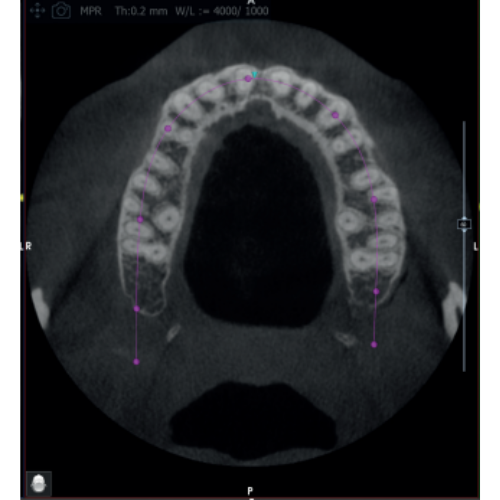

X-MIND® optima 3D represents the perfect combination of advanced hardware technology, enclosed in a lightweight and compact design and next-generation software, RealGuide™ 5.4, bringing the benefits of Artificial Intelligence into every step of patient care, from a precise diagnosis to more effective treatments and patient communication.

- Field Of View: 5x5, 8.5x5, 8.5x9, 12x10

- 2D and 3D Imaging

- Multi FOV

- Adjustable FOV

- Focused FOV

- Large FOV